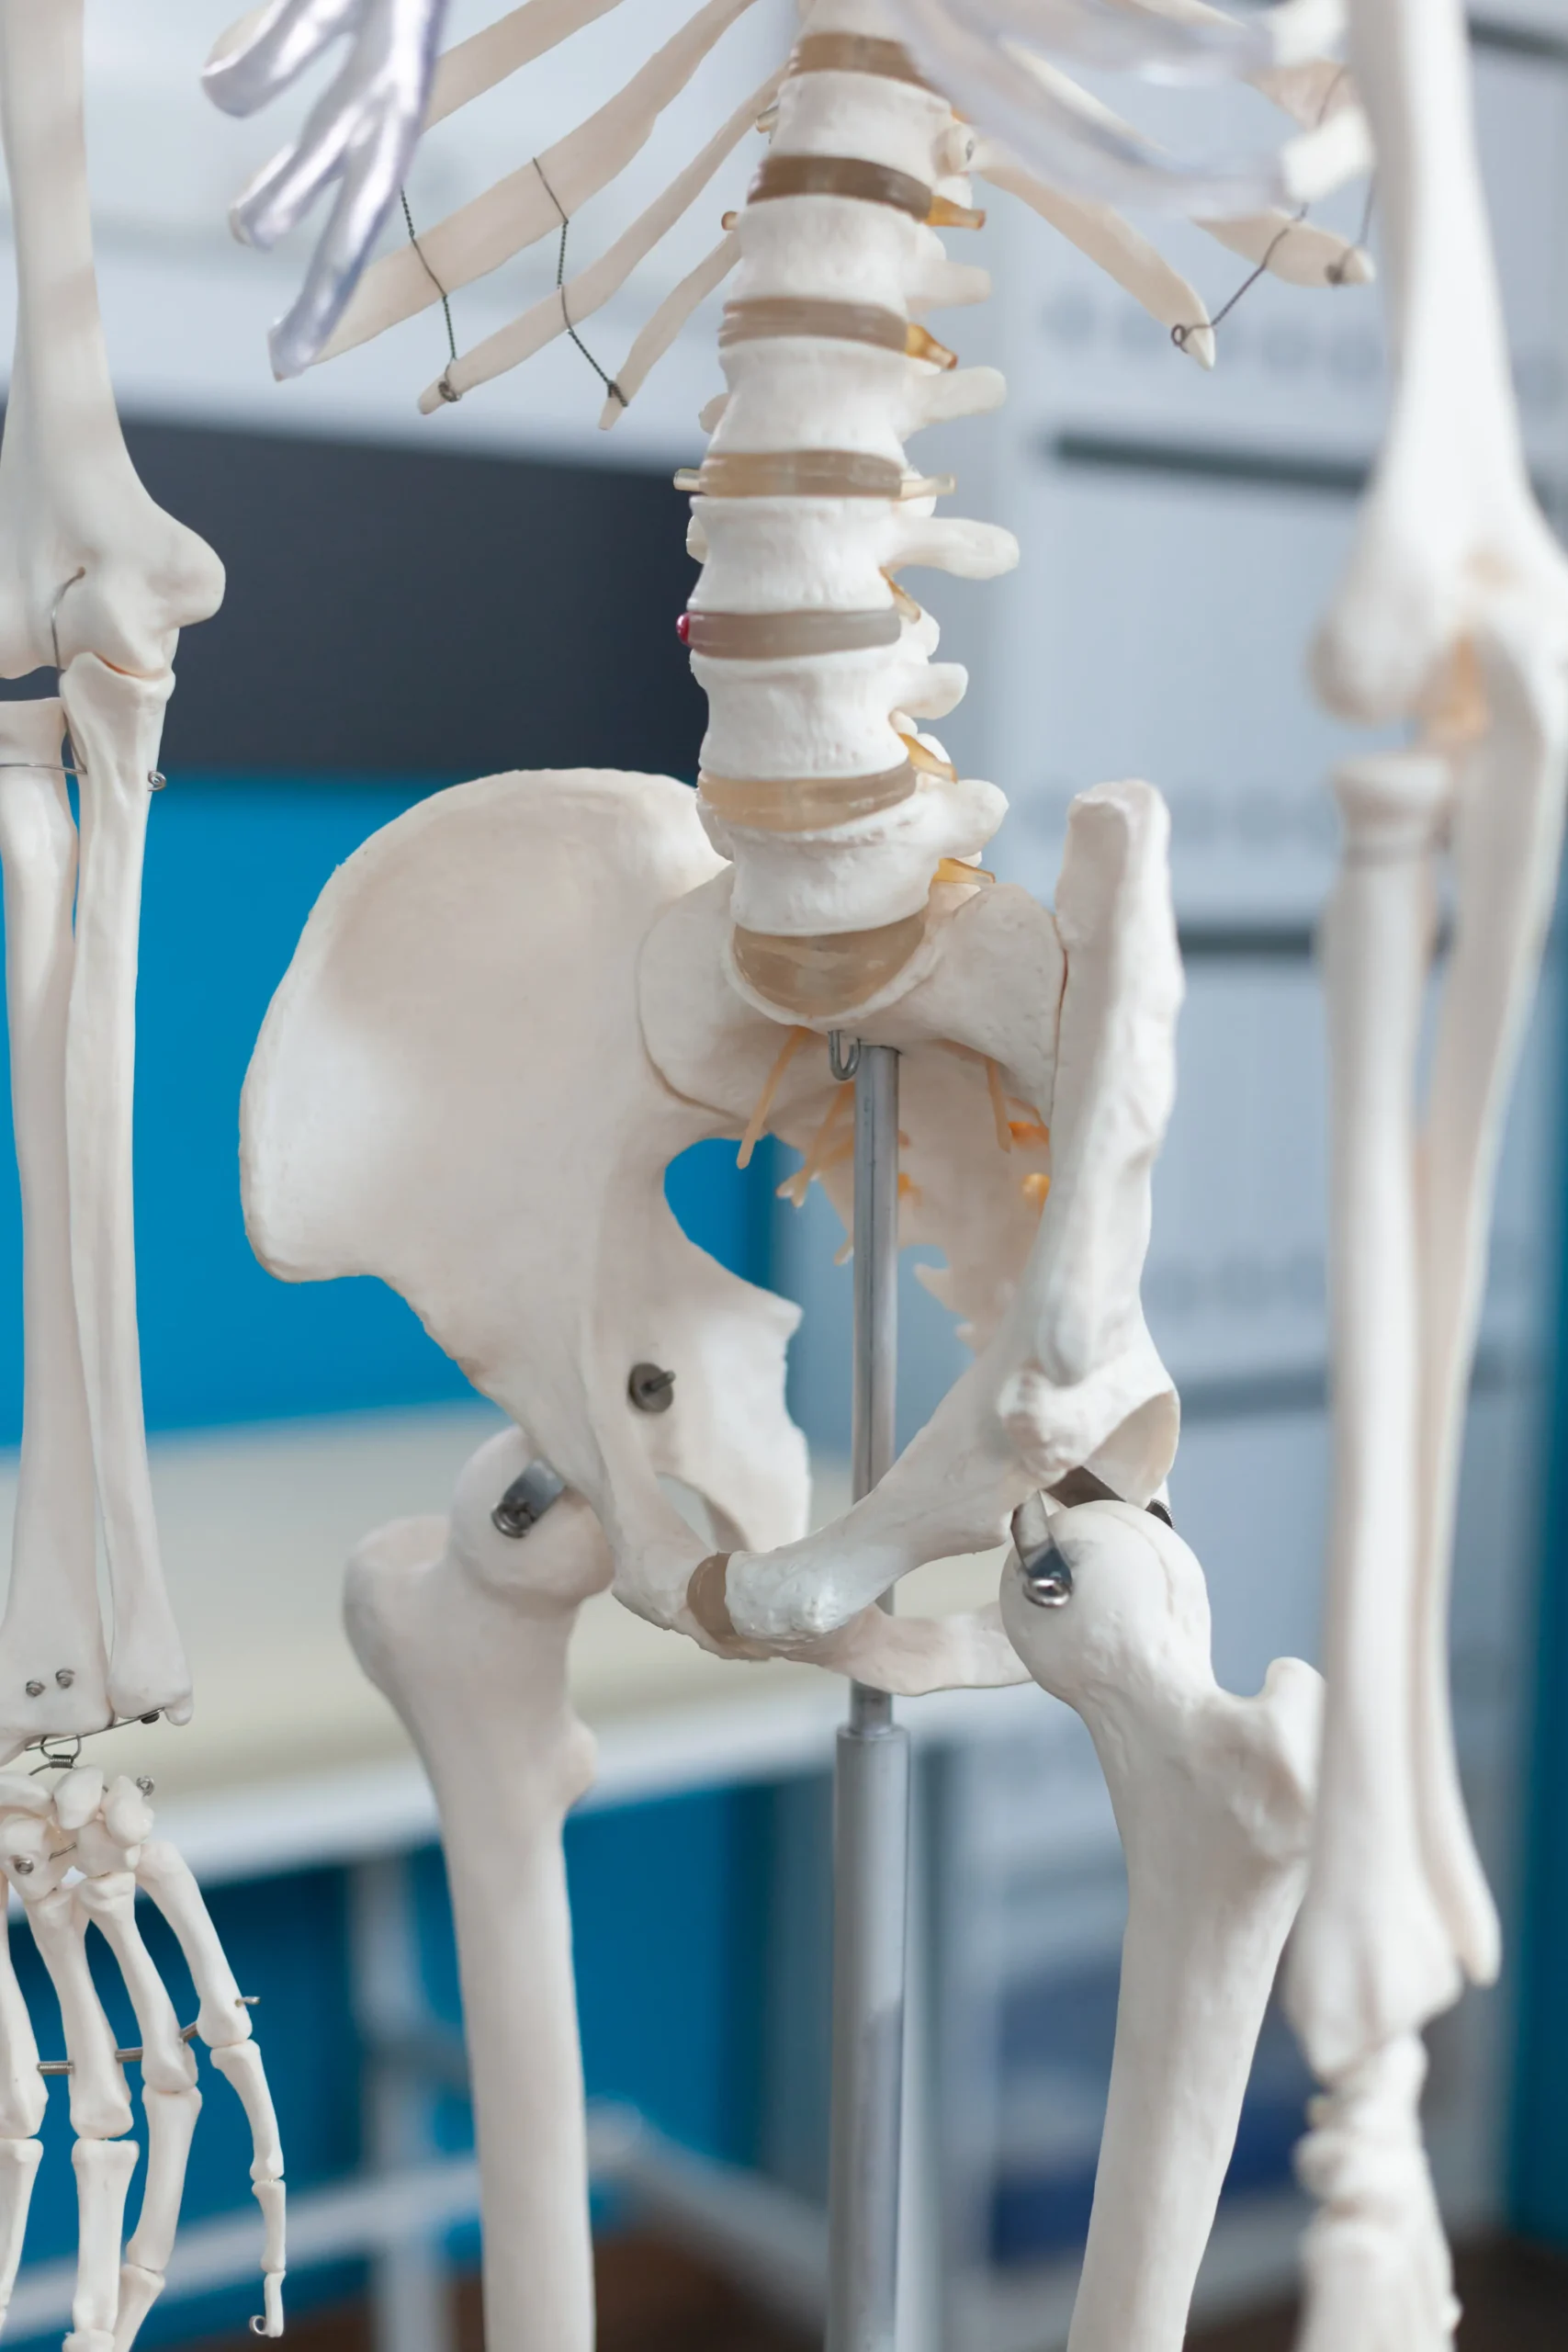

Total Hip Replacement

Our Total Hip Replacement procedures use modern prosthetics and minimally invasive methods to relieve pain and restore full motion. We prioritize faster recovery and long-term joint performance, helping patients return to an active lifestyle with confidence.